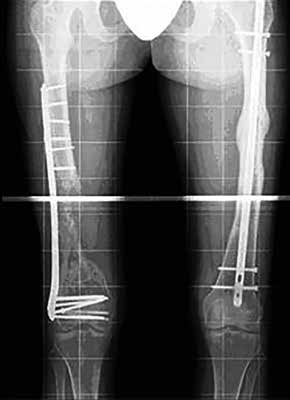

Handelt es sich jedoch um schwere langstreckige Verletzungen, die teilweise neben den Bandrekonstruktionen auch knöcherne Stabilisierungen mit Platten-/Schraubensystemen erforderlich machen, scheint der Gipsabdruck immer noch das Mittel der Wahl zu sein. Dabei muss vom versierten Techniker die Längenbestimmung der Schalen am Ober- und Unterschenkel festgelegt werden, um z. B. kritische Zonen bei Plattenstabilisationen und Kraftspitzen bei einer wiederaufgenommenen sportlichen Aktivität mit großen Hebeln zu vermeiden. Dies ist gerade im alpinen Skilauf ein wichtiger Faktor (Abb. 7a u. b).